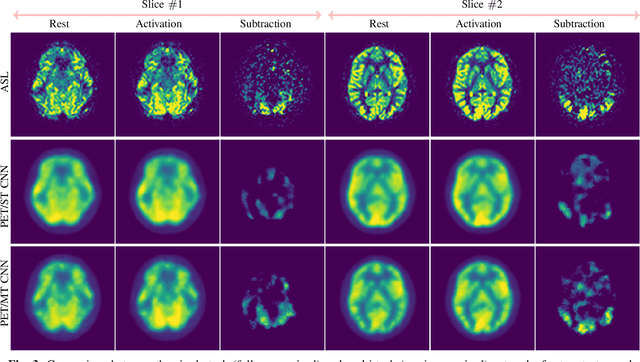

Abstract:Positron Emission Tomography (PET) is an imaging method that can assess physiological function rather than structural disturbances by measuring cerebral perfusion or glucose consumption. However, this imaging technique relies on injection of radioactive tracers and is expensive. On the contrary, Arterial Spin Labeling (ASL) MRI is a non-invasive, non-radioactive, and relatively cheap imaging technique for brain hemodynamic measurements, which allows quantification to some extent. In this paper we propose a convolutional neural network (CNN) based model for translating ASL to PET images, which could benefit patients as well as the healthcare system in terms of expenses and adverse side effects. However, acquiring a sufficient number of paired ASL-PET scans for training a CNN is prohibitive for many reasons. To tackle this problem, we present a new semi-supervised multitask CNN which is trained on both paired data, i.e. ASL and PET scans, and unpaired data, i.e. only ASL scans, which alleviates the problem of training a network on limited paired data. Moreover, we present a new residual-based-attention guided mechanism to improve the contextual features during the training process. Also, we show that incorporating T1-weighted scans as an input, due to its high resolution and availability of anatomical information, improves the results. We performed a two-stage evaluation based on quantitative image metrics by conducting a 7-fold cross validation followed by a double-blind observer study. The proposed network achieved structural similarity index measure (SSIM), mean squared error (MSE) and peak signal-to-noise ratio (PSNR) values of $0.85\pm0.08$, $0.01\pm0.01$, and $21.8\pm4.5$ respectively, for translating from 2D ASL and T1-weighted images to PET data. The proposed model is publicly available via https://github.com/yousefis/ASL2PET.